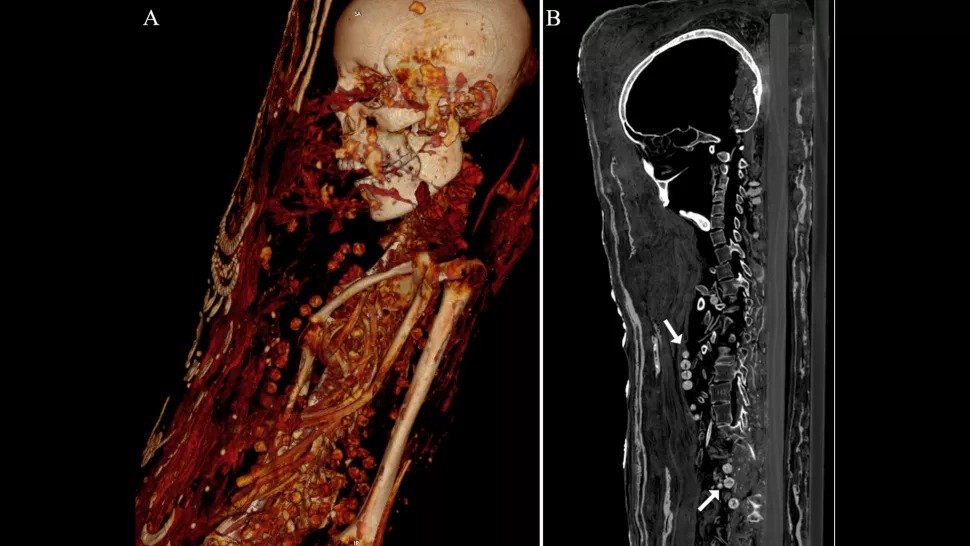

CT(コンピューター断層撮影)スキャンは、3つの石膏でコーティングされたミイラのうちの1つが器官(脳さえ)で埋められ、2人の女性が美しいネックレスで埋められたことを示しています。

CTスキャンは女性の首と体にネックレスのビーズを示しています。 (Zesh et al。、PLOS One、2020)。

コンピュータ断層撮影法は、ミイラ化した人々-男性、女性、10代の少女がローマ時代後期(紀元前30年-西暦395年)に住んでいたことを示しました。

CTスキャンはまた、女性の関節炎を含むいくつかの健康上の問題を明らかにしました。

コンピュータ断層撮影は、男性が25歳から30歳の間に死亡したことを示しました。 彼の身長は約163センチで、2つの破裂していない臼歯といくつかの骨のひびがありました。

30歳から40歳の間に亡くなった女性の身長は約151cmで、左膝に進行性関節炎がありました。 コンピューター断層撮影によると、このティーンエイジャーは17歳から19歳の間に亡くなり、身長は約156cmでした。

研究者によると、彼女は脊椎血管腫として知られる良性の腫瘍を脊椎に持っていました。これは40歳以上の人々によく見られます。